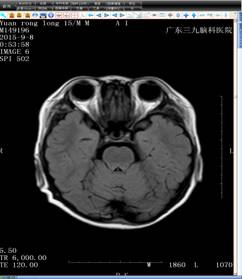

结合小袁的病史,神经内二科的钟水生主任考虑其存在垂体柄阻断综合征的可能(图一),并建议补充垂体薄层平扫+增强扫描(图二)。完善检查后,钟主任给予小袁B族维生素、申捷促进神经修复等对症治疗。

头颅MRI T2+FLAIR+增强(图二)